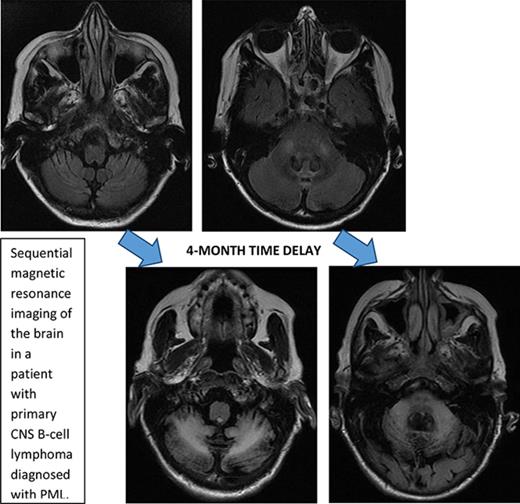

Initial symptoms included limb weakness (5 patients), visual loss (3 patients), cognitive impairment/behavior change (4 patients), and a cerebellar syndrome (4 patients). Magnetic resonance imaging abnormalities were restricted to the cerebrum in 12 patients; 2 patients had abnormalities restricted to the cerebellum and brainstem (Figure 1), and 2 patients had abnormalities in both the cerebrum and the brainstem and cerebellum.